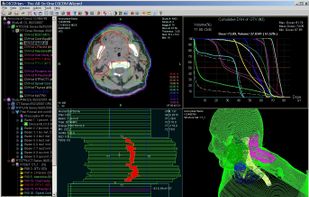

All-In-One DICOM Wizard for Radiation Oncology and Radiology. DICOMan is a DICOM/DICOM-RT viewer enhanced with a set of built-in tools such as DICOM Decompressor, DICOM Pusher, DICOM Retriever, DICOM Editor, DICOM Anonymizer, DICOM Format Converter and so on. DICOMan is such a s.